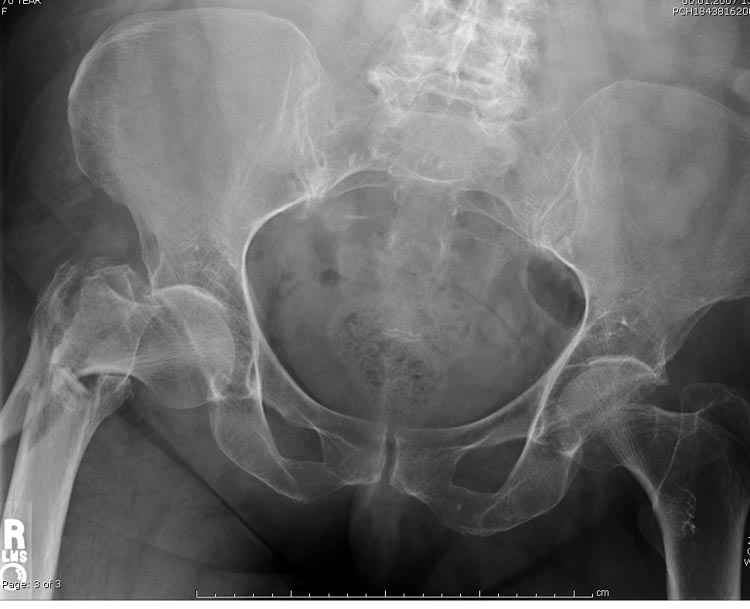

Предугадать распространение линий перелома при чрезвертельных и оскольчатых переломах трудно, поэтому для принятия правильного решения рекомендуется Компьютерно Томографические исследование.

При отсутствии КТ, снимок на вытяжении поможет увидеть общую картину расположения отломков, особенно потенциальные места введения импланта. Риск раскола в этом случае огромный, поэтому больной должен быть дообследован.

А так для лечения оскольчатых переломов подходят все методы, включая интра- и экстрамедуллярные в зависимости от опыта и наличия импланта.

Здесь пара похожих случаев.